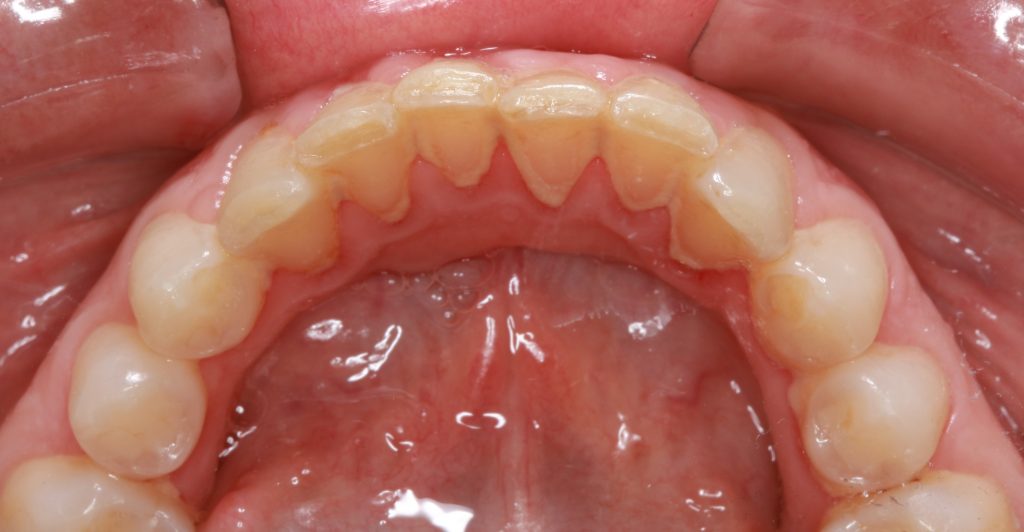

En el primer control que fue a los 15 días se evaluó si los dientes tenían el espacio suficiente para alinearse y se pudo apreciar un notorio avance en el alineamiento (Fig.2). El segundo control (Fig.3) se dio a los 6 días y en él, se realizó con una lija metálica un ligero stripping en los puntos donde había mucha presión interproximal. Finalmente, se le dió una cita a la semana para colocar el mantenedor fijo. (Fig.4). El tratamiento duró 1 mes debido a que el apiñamiento era leve.

Segundo control (a los 6 días del 1er control)

Tercer control- Final (1 semana después)